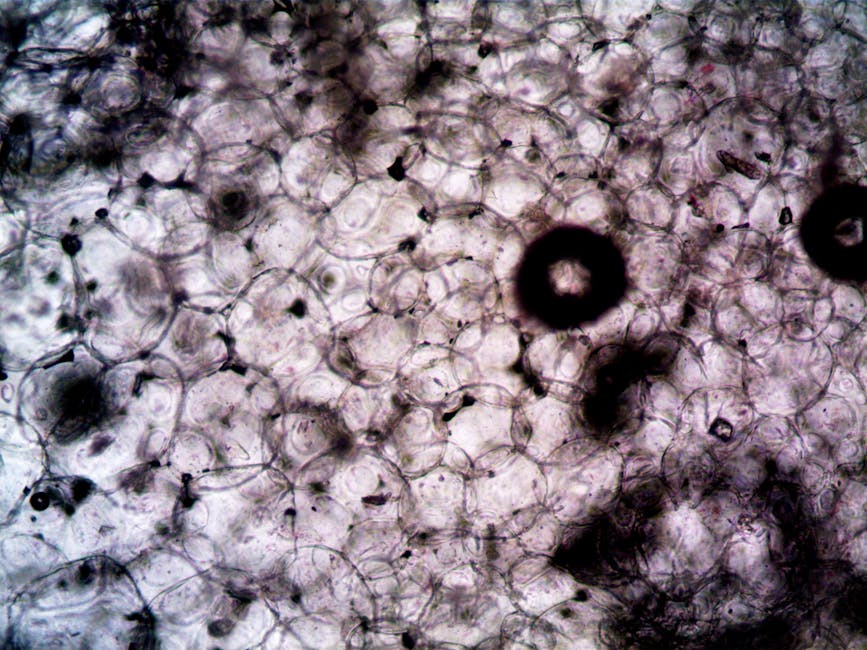

How Aggressive Breast Cancer Turns Off the Immune System